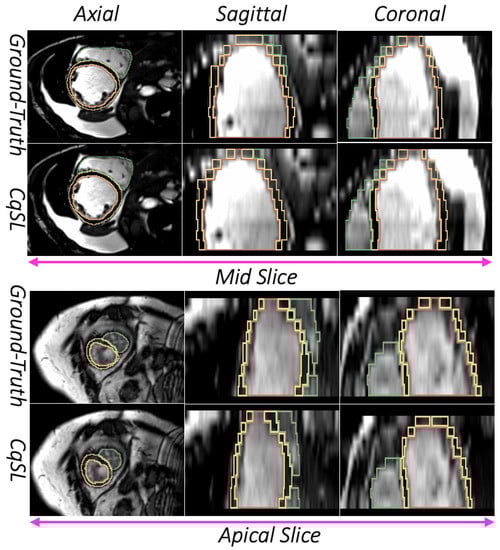

3.1. Image Segmentation Assessment